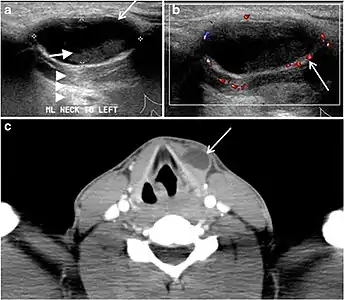

Fig. 16. Midline ectopic thyroid with Hashimoto's thyroiditis in a 49-year-old female patient. a Transverse greyscale ultrasound shows a 1.6 × 0.8 cm solid, well-defined, heterogeneous area (white arrow) in the midline, superior to the thyroid gland. It is iso-echogenic to the thyroid gland with no definite connection to the thyroid gland. b Transverse colour Doppler ultrasound shows significant increase in vascularity. c Axial enhanced neck CT scan at the level of thyroid cartilage demonstrates midline infrahyoid hyperdense soft tissue mass (white arrow) embedded within the strap muscle.[1]